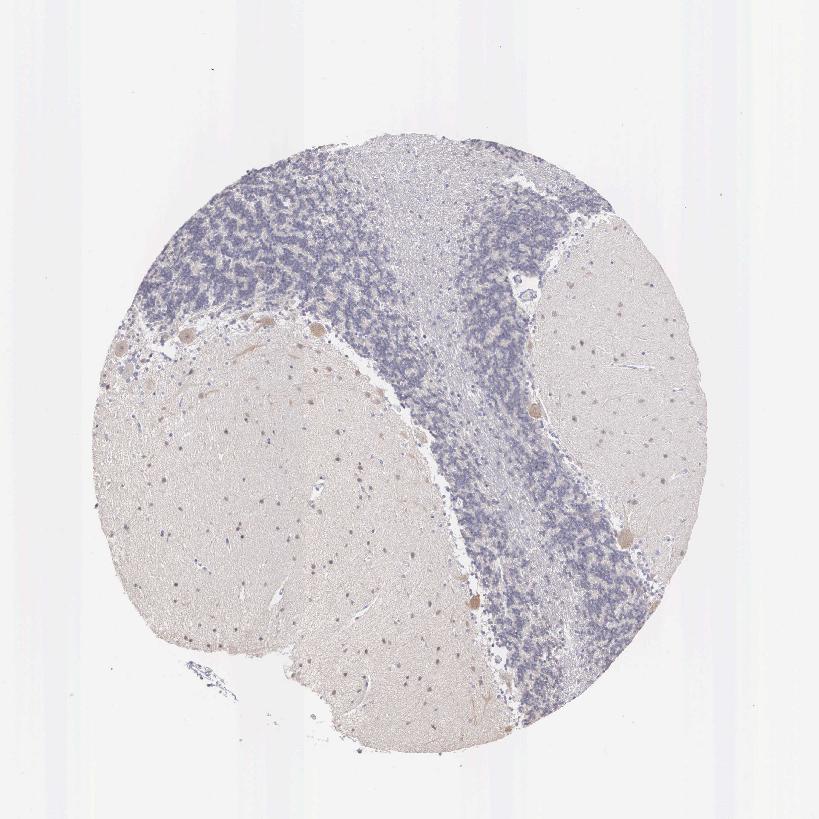

CEREBELLUM - Antibody stainingi

Antibody staining in the annotated cell types in the current human tissue is reported as not detected, low, medium, or high, based on conventional immunohistochemistry profiling in selected tissues. This score is based on the combination of the staining intensity and fraction of stained cells.

Each image is clickable and will lead to virtual microscopy that enables deeper exploration of all samples and also displays staining intensity scores, fraction scores and subcellular localization as well as patient and tissue information for each sample.

Antibody HPA000565Antibody HPA026073

Purkinje cells MediumNot detected

Cells in granular layer Not detectedNot detected

Cells in molecular layer LowNot detected